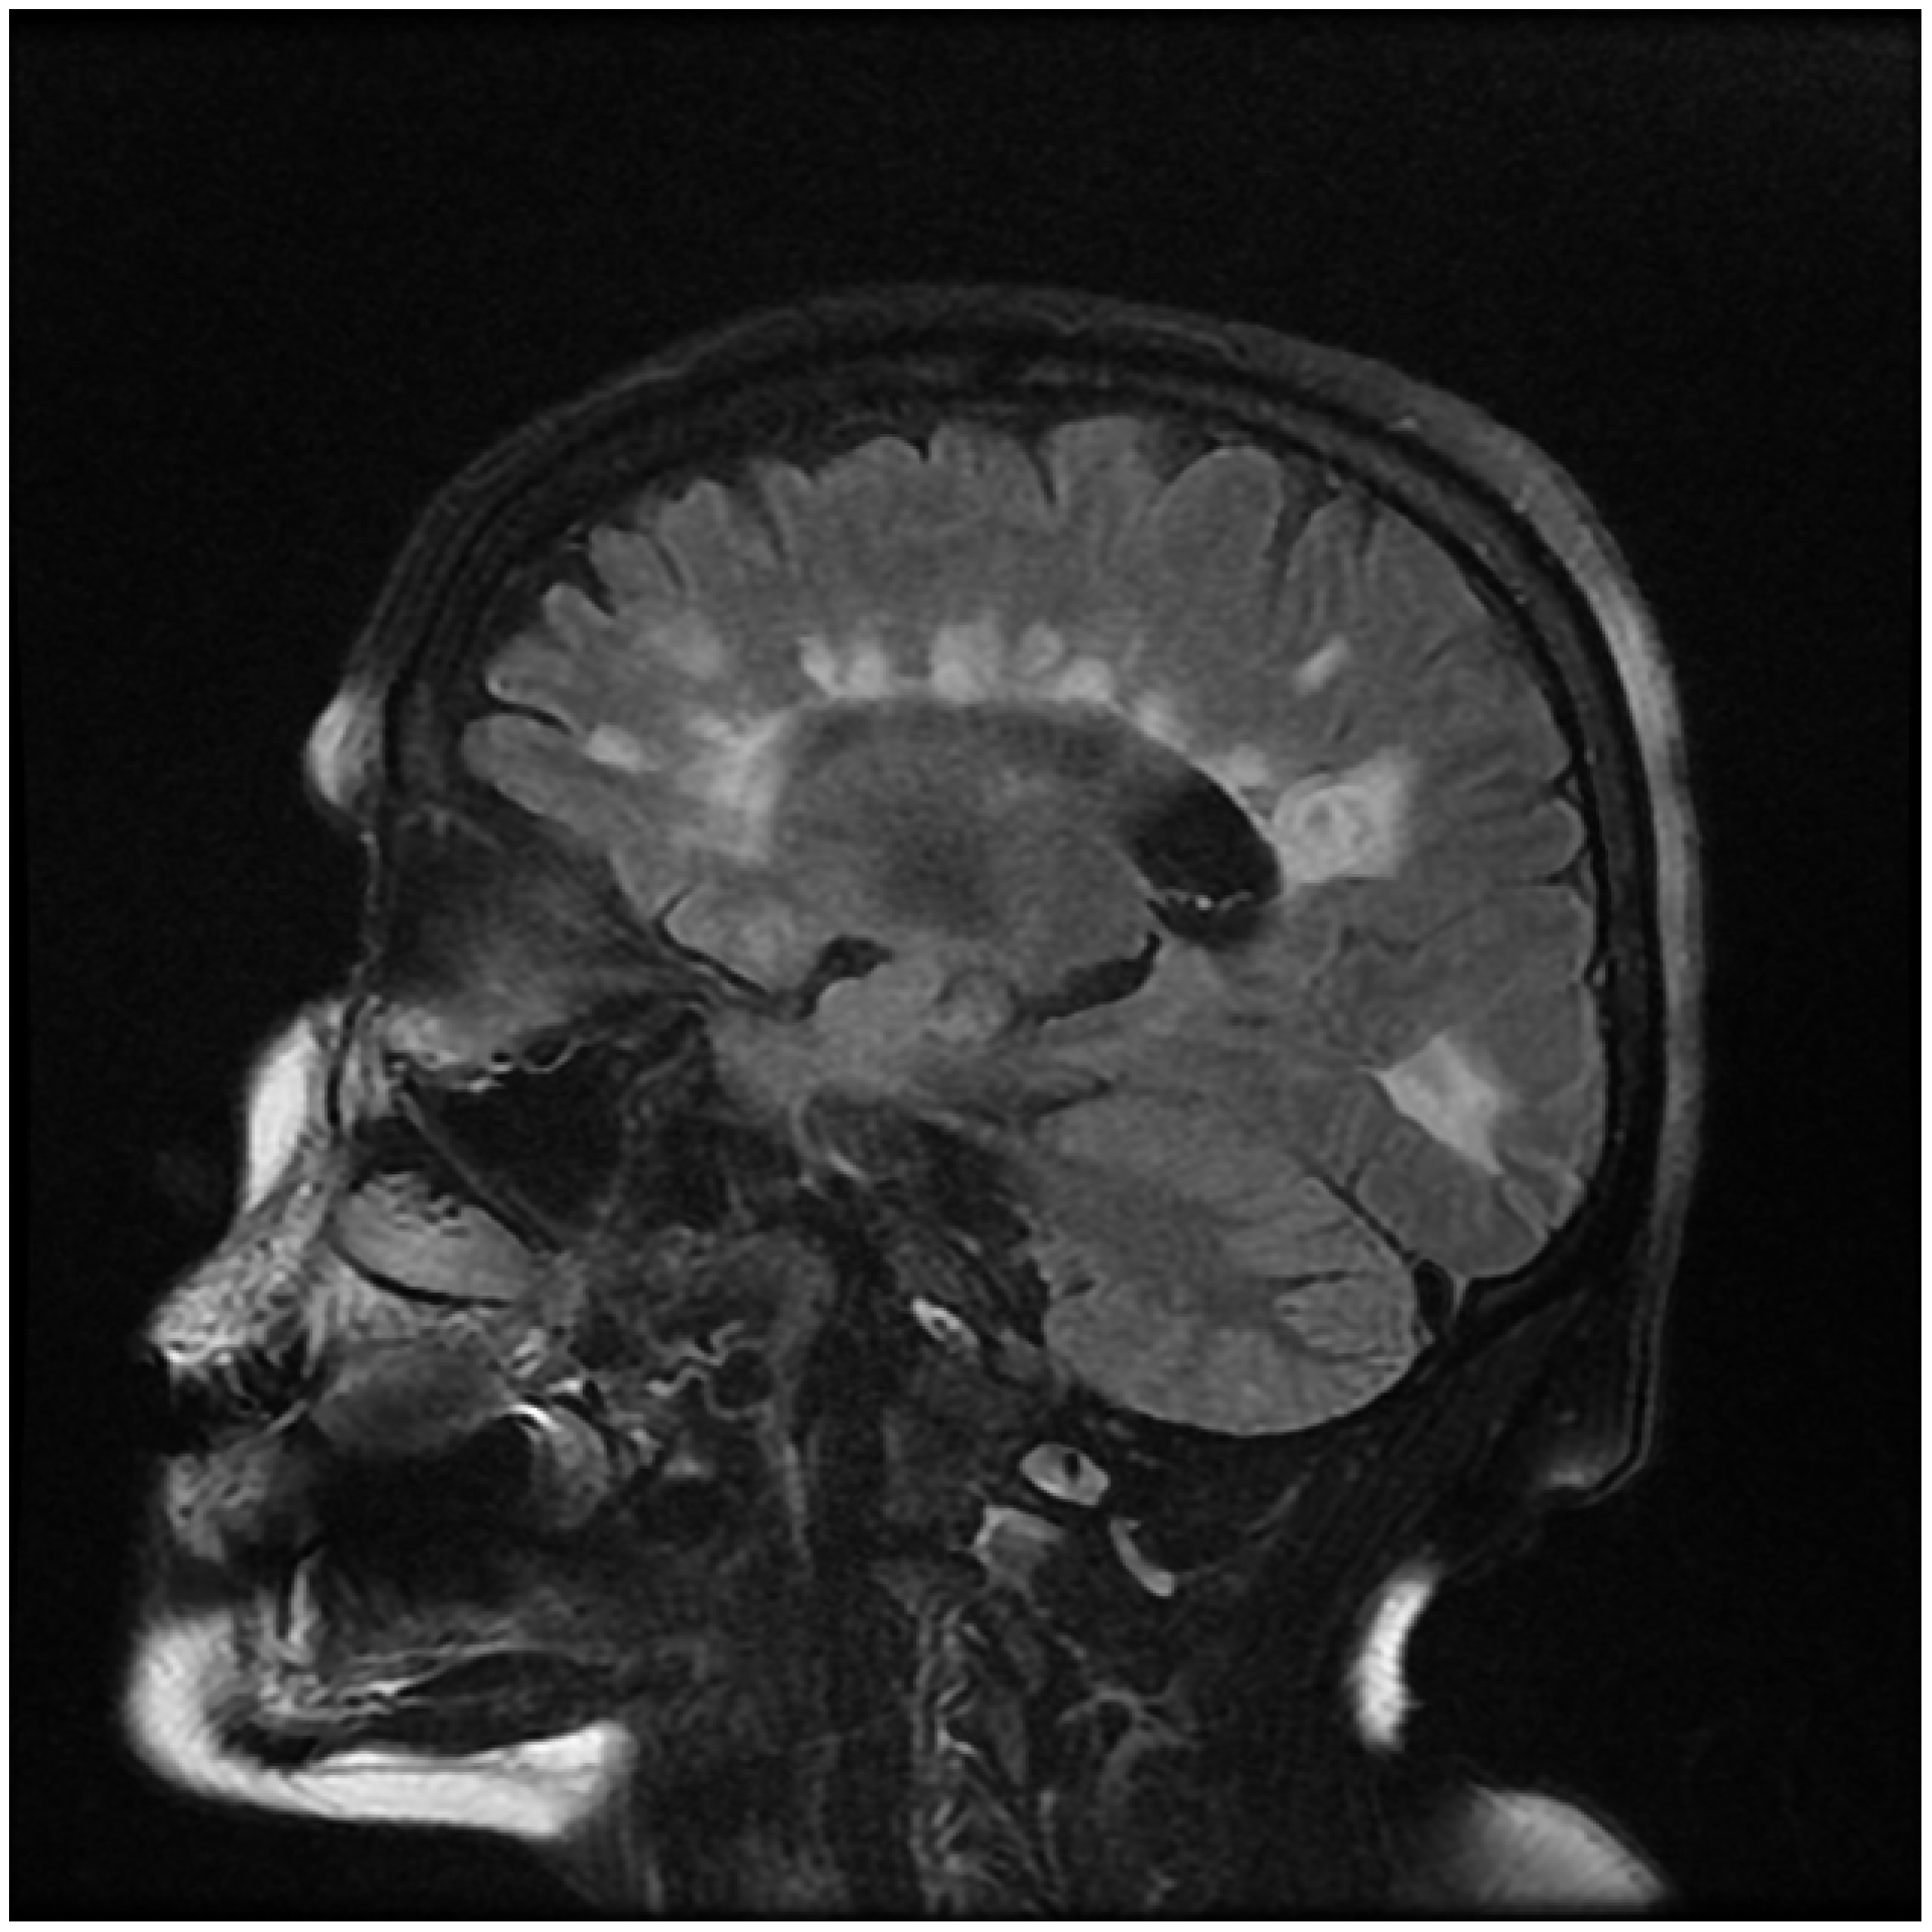

In this model, demyelination occurs in clusters, simulating a more localized or regional impact on the network. This contrasts with the earlier model where demyelination was distributed more randomly across the entire network. This approach reflects certain pathological patterns seen in some neurological conditions where damage may be concentrated in specific areas rather than being uniformly distributed as Figure 5. Clearly shows below.

Figure 5. Periventricular Clustered Sagittal Image in Human MRI showing clustered periventricular white patches lesions commonly known as Dawson’s Fingers”. Source: Radiopedia.